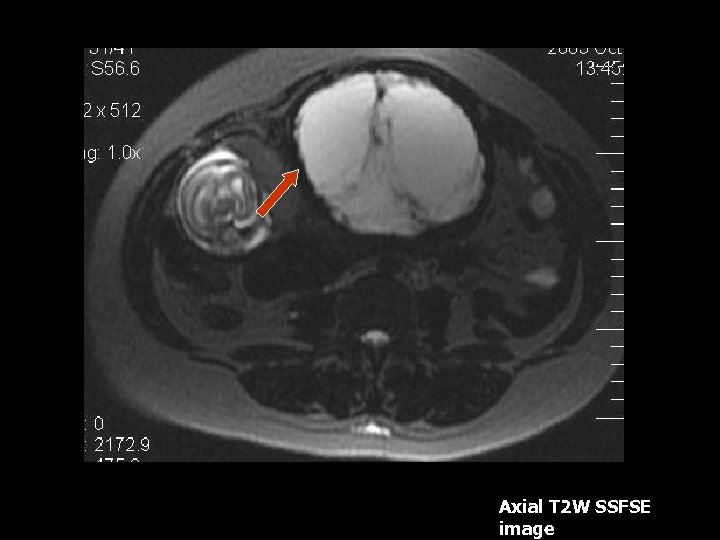

Axial SSFSE T 2 W image

Mature Cystic Teratoma • 25 -58% of all benign ovarian tumors, 70% if age <19 (6). • Dermoids contain mesodermal, ectodermal and endodermal elements (6). • Typically an epithelial lined cyst filled with sebaceous fluid, debris and hair (6). • Intralesional mural nodule(Rockitansky nodule) is identified in >90% which may contain fat, teeth(7%)or calcifications(18%) (6). • Common complication: Torsion which occurs in 16% of cases(6). • Rare complication: Rupture(1%), Infection(1%), Autohemolytic anemia(1%), Malignant transformation(12%) (6). • Malignant transformation should be suspected if size greater than 10 cm and postmenopausal age(6).

Mature Cystic Teratoma • Characteristic MR features: Fat within the teratoma can be diagnosed with T 1 weighted, T 1 with fat suppression(2, 4). • Other MRI findings: Fat-fluid levels, dermoid nipple or mural nodule, and intracystic fat balls(7). • Calcium and bone is present will demonstrate low intensity on all pulse sequences(7).